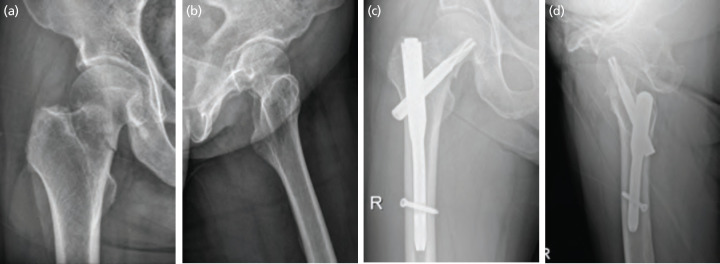

Material and methods: Among elderly patients with Garden type 1 and 2 FNFs treated between January 2010 and May 2018, 44 who were followed-up for more than 1 year were included. There were 28 cases in the CTS group and 16 cases in the CMN group, and the average age at the time of surgery was 76.3 years (range, 65-88 years). Radiological and functional variables were analysed to compare the results by fixation device.

Results: There were no significant differences between the groups in terms of functional outcomes or bone union times. However, operation and fluoroscopy times were significantly shorter in the CMN group. The neck shaft varus angulation and the extent of device sliding were greater in the CTS group. Multivariate analysis showed that CTS use was independently associated with major complications.

Conclusion: The CMN is a useful tool for treating stable FNFs in the elderly. It is simpler to use than conventional CTS fixation and is associated with fewer complications.